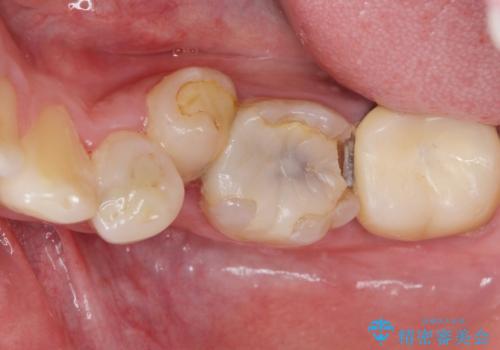

- 下の奥歯が内側に生えていることを主訴に来院された患者様です。

精査したところ、左下の小臼歯(左下5)が舌側転位しており、また隣の歯の詰め物は欠け虫歯になっていました。

矯正は絶対にしたくないという強いご希望により、舌側転位している歯を抜去し歯肉の治癒を待ったのち、両隣の歯の補綴治療を行いました。